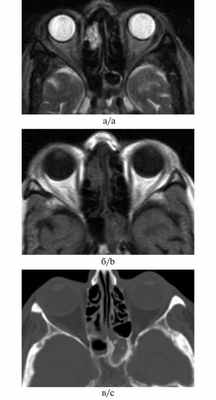

При магнитно-резонансном исследовании пациентки с фунгозным сфеноидитом патологические изменения выглядели гиперинтенсивными на Т1-взвешенном изображении при отсутствии измененного сигнала на Т2-взвешенном изображении, что создавало впечатление о нормальной пневматизации пазухи (рис. 9). Рис. 9. Больная М., 81 год. МРТ и рентгеновская КТ в аксиальных проекциях. На Т2-взвешенном изображении (а) отсутствует сигнал и складывается впечатление о нормальной пневматизации клиновидной пазухи слева, в то время как на Т1-взвешенном изображении и КТ-изображении патологическое содержимое в синусе присутствует (б, в). The T2-weighted image (а) demonstrates the absence of the signal and produces the impression of normal pneumatization of the left-hand sphenoidal sinus whereas neither the T2-weighted image nor the CT-image shows any pathological content in the sinus (b, c).